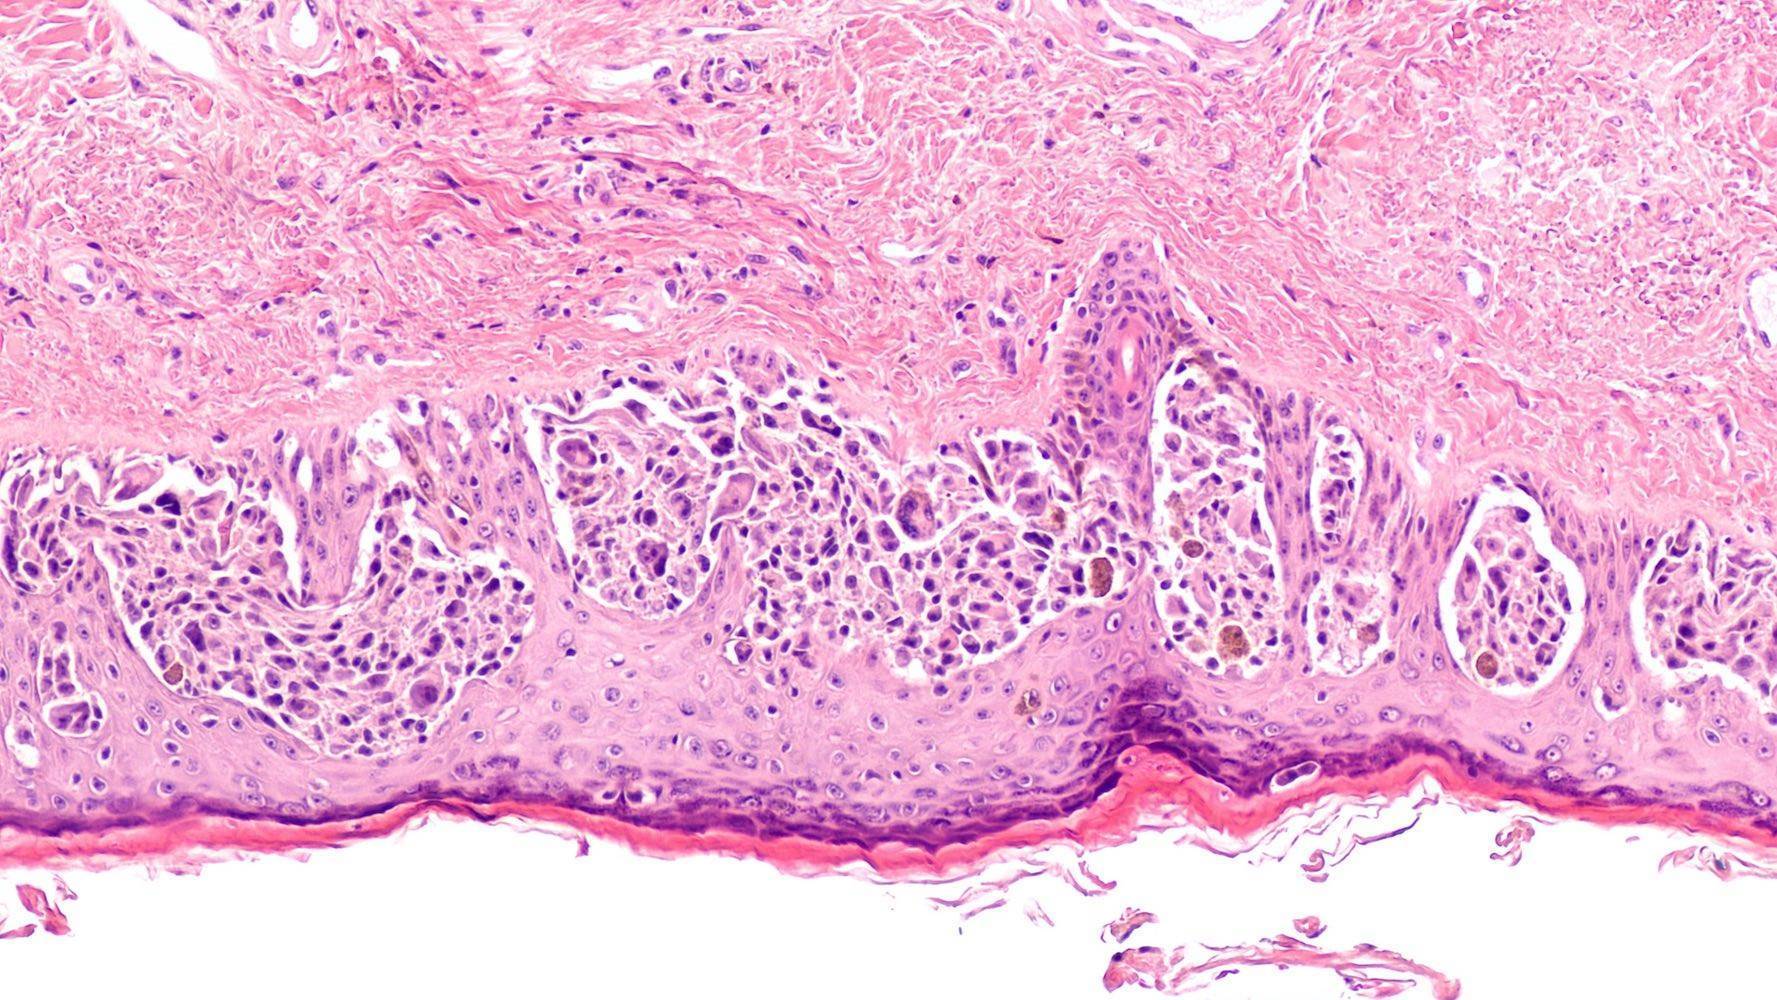

Bilder von Hautkrebs

Bilder von Hautkrebs können helfen, die Art der Erkrankung zu bestimmen. Das Basalzellkarzinom kann rosa, rot oder weiß sein und wird meist mit einem einfachen Hautausschlag verwechselt. Plattenepithelkarzinome können rot oder braun sein und ähneln in ihrem Aussehen einem Ekzem. Ein Melanom kann überall am Körper auftreten und kann mit einem normalen Leberfleck verwechselt werden.

Diagnose weißer Hautkrebs – wie sieht er aus?

Zum weißen Hautkrebs gehören Formen wie Basalzellkarzinome und spinozelluläre Karzinome. Er tritt häufig an Hautstellen auf, die lange Zeit der Sonne ausgesetzt sind, wie das Gesicht. Bei Männern mit Glatze ist die Kopfhaut am häufigsten von dieser Krankheit betroffen. Am Körper tritt der Krebs meist an den Handrücken oder am Rumpf auf. (5)

Diagnose schwarzer Hautkrebs – wie unterscheidet er sich von weißem?

Schwarzer Hautkrebs, auch malignes Melanom genannt, ist die gefährlichste Form von Hautkrebs, da er meist erst in einem viel späteren Stadium entdeckt wird. Ein weiterer Unterschied zwischen den beiden Krebsarten ist, dass schwarzer Hautkrebs seltener vorkommt als weißer Hautkrebs. Er kann an allen Stellen des Körpers auftreten, auch an der Schleimhaut.